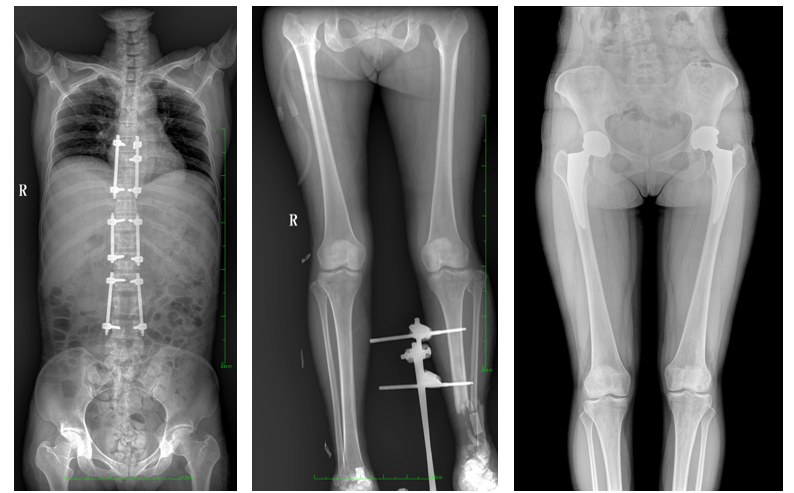

DR常用于人体胸部及骨骼摄片,也可拍摄其他部位,例如腹部、牙齿、头颅等。使用人群较广,可以进行全身各部位检查,曝光后几秒就可获得数字影像,成像速度快,且价格便宜,极大提高了工作效率,方便临床重症、急症患者的诊治。

站立位X线影像是测定人体负重骨骼的生物学力线、对称结构平滑线及脊柱侧凸角等首选的检查内容,这和CT、MRI卧位成像,在临床意义上有着根本区别。在脊柱及下肢的临床治疗过程中,一般需要进行矫正和关节置换手术治疗,在对其进行手术前后,均需要拍摄站立位负重X光片以便分析病情,明确诊断和观察治疗效果。

常规DR拍摄面积有限,最大规格仅有43cm,但成人男性全脊柱长度平均为70-75cm,女性为66-70cm,而双下肢更长。普爱医疗PLX8600动态DR的43cm*86cm超大有效视野,可一次成像全脊柱及双下肢。